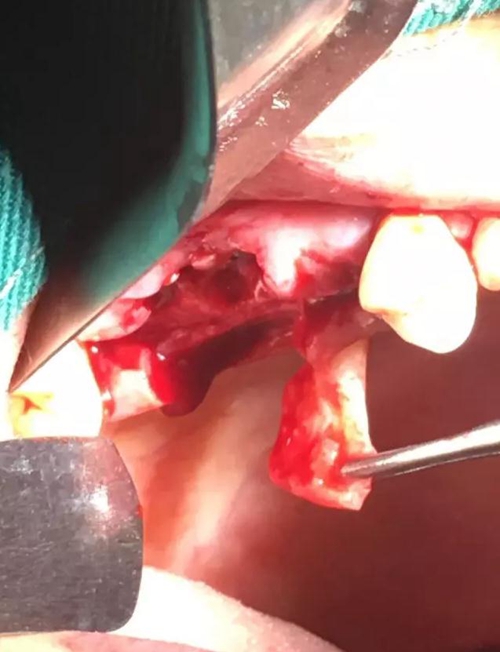

【病例分享】?jī)?nèi)提,用自體骨柱,不用骨粉

2.jpg